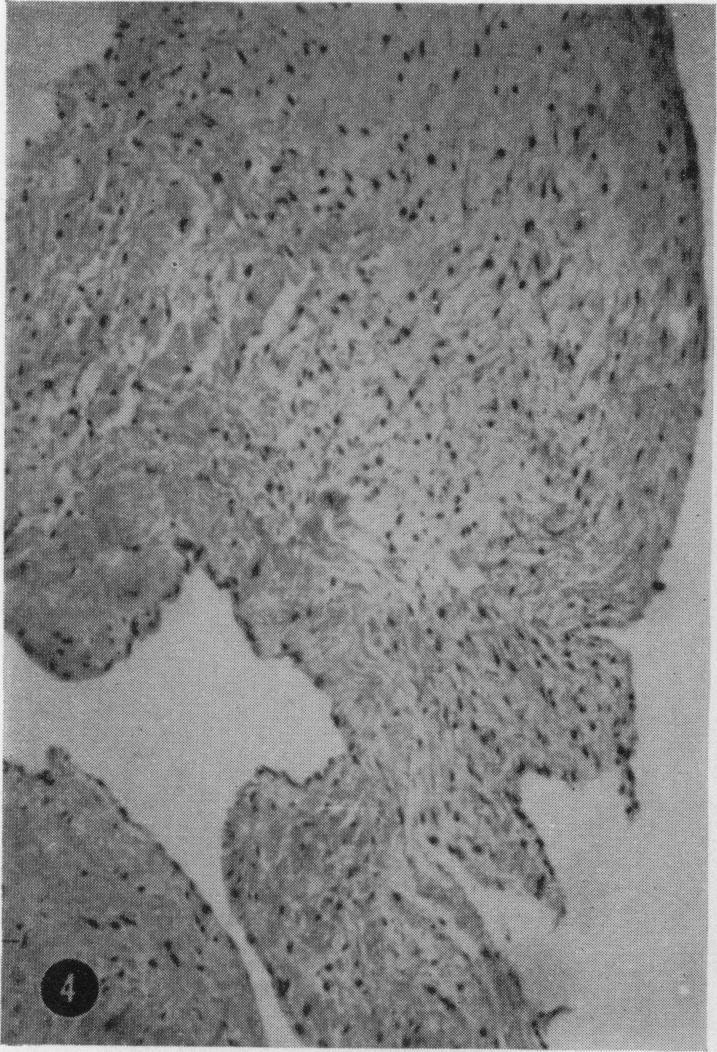

Coxsackie virus B4 pancarditis in cynomolgus monkeys resembling rheumatic heart lesions.

Experimental Coxsackie virus B4 valvulitis in cynomolgus monkeys.

Am Heart J. 1966 May;71(5):678-83. doi: 10.1016/0002-8703(66)90319-x.